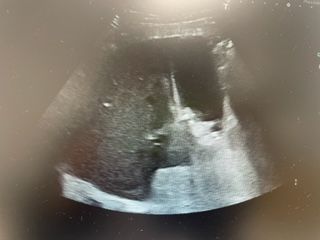

Ante la elevación de transaminasas y de bilirrubina total (no vistos en AS previas), se decide realizar Ecografía Clínica a pie de cama, donde se objetiva vesícula biliar con aumento del grosor de su pared, así como estructuras hiperecogénicas, con sombra acústica posterior, sospechosas de colecistitis.

Ante la sospecha de colecistitis, se comenta el caso con CGD y el paciente es ingresado en planta.